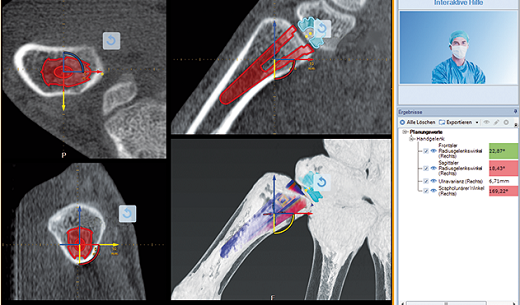

Quy trình lập kế hoạch phẫu thuật chấn thương chỉnh hình bàn tay được đơn giản hóa bằng mô-đun MediCAD® Hand 3D. Hình ảnh X-quang, CT, MRI hoặc DVT có thể được sử dụng để dễ dàng thấy được tình trạng bệnh lý của bàn tay, cổ tay và ngón tay, và bằng cách sử dụng mô-đun này các bước kế tiếp có thể được lên kế hoạch một cách tối ưu.

+ Chế độ xem Transparent và kiểm tra tiếp xúc giữa implant và xương

Chế độ xem Transparent nâng cao khả năng quan sát các mô cấy ở các vị trí tương ứng của bạn. Thông thường bác sĩ cần xác định trực quan tình trạng của xương tại vị trí cấy ghép dự kiến. Bác sĩ có thể thực hiện với các đơn vị Hounsfield của xương.

Bác sĩ dễ dàng đánh giá mật độ xương cao hay thấp và có thể quan sát tại vị trí cấy ghép theo kế hoạch. Do đó, xương sau khi cấy ghép có độ ổn định cao. Hình dung khoảng cách của các đơn vị Hounsfield có thể được sử dụng để lập kế hoạch trước phẫu thuật, cho phép bác sĩ xác định kỹ thuật chuẩn bị chính xác và giải pháp phục hình tiếp theo.

+ Dễ dàng dể hình dung việc cấy ghép implant trong xương bằng chế độ xem xuyên thấu

Nhờ các tùy chọn đa dạng do phần mềm chấn thương chỉnh hình 3D Hand cung cấp, các bộ phận cấy ghép riêng lẻ có thể được lắp ráp với sự trợ giúp của bộ tạo hình bộ cấy ghép và đặt vào mô hình 3D (hình ảnh CT của bệnh nhân). Hơn nữa, các mô cấy có thể được điều chỉnh, xoay, di chuyển hoặc thay đổi sang loại mô cấy khác theo nhóm hoặc đối tượng riêng lẻ.

Các video hướng dẫn và trợ giúp tương tác có sẵn trong suốt quá trình lập kế hoạch của phần mềm phẫu thuật MediCAD® Hand 3D cung cấp cho bác sĩ bản trình bày sơ đồ và danh sách tất cả các bước cần thiết, khiến cho công việc của các bác sí phẫu thuật dễ dàng và hiệu quả hơn nhiều.